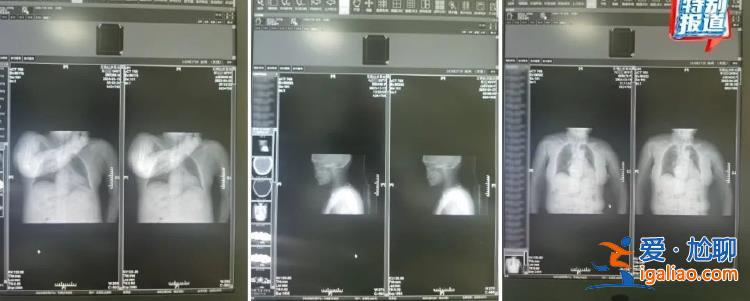

朱醫生懷疑醫院涉嫌偽造病歷,騙取醫療保險。今年3月,他將沒有影像號的病歷拍照留證,向醫院上級管理部門實名舉報。在等待調查結果時,他舉報的這些病歷又有了影像號和片子。隨之,他發現了更多問題,包括:

多名患者和他人影像高度相似

影像與診斷左右方向對應錯誤

被舉報后,補的虛假影像和虛假影像號。